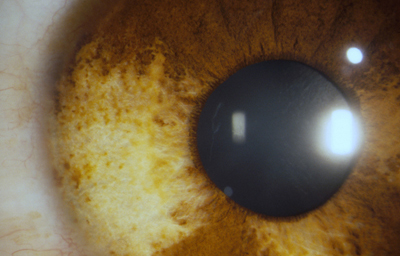

El Color del Iris

El Iris en general es muy pigmentado con colores que comúnmente van del marrón, avellana, gris, verde y azul. Existen los iris sin pigmento en el Albinismo oculo-cutáneo en cuyo caso se ven blanco/rosados.

El color del Iris es un fenómeno complejo por efectos combinados por la textura, la pigmentación y el tejido fibrovascular del estroma, junto con la constitución epigenética del individuo. Desde el punto de vista óptico, la simple absorción o reflexión selectiva por algunas moléculas, como la hemoglobina o el colágeno del estroma que son componentes no pigmentados, puede tener influencia en el color que es observado.

A pesar de la gran variedad en el color del Iris, el único pigmento que contribuye en forma sustancial es la melanina; su cantidad, es uno de los factores que determina el color del iris en una persona. Estructuralmente el color depende de la cantidad variable de eumelanina (melaninas marron/negra) y pheomelanina (melaninas rojo/amarillo) producidas por los melanocitos derivados de la Cresta Neural. El grado de dispersión de la melanina que yace en racimos subcelulares en los melanosomas, tiene cierta influencia en el color que se observa, pero el grado de dispersión no es reversible ya que los melanosomas no son moviles.